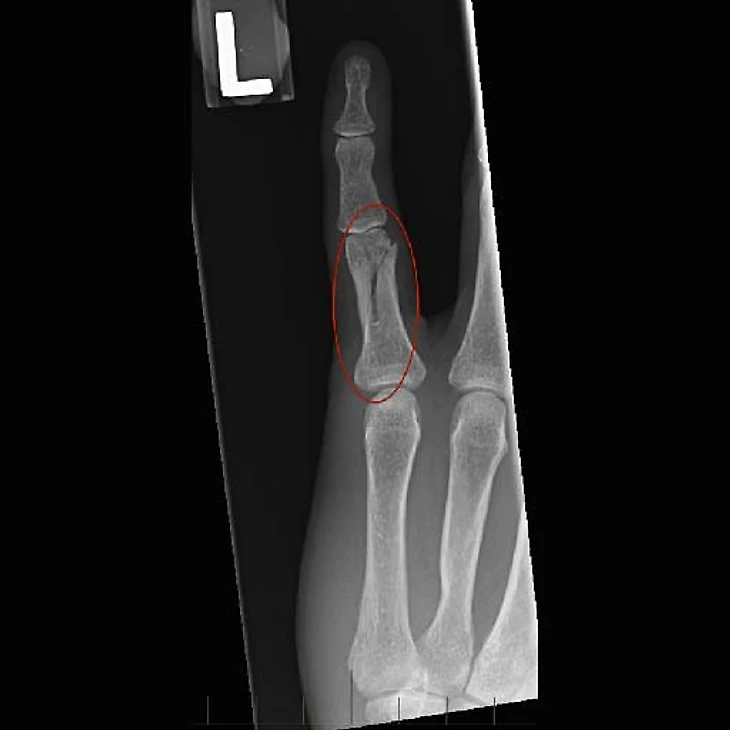

Удар по кончику пальца. Такой механизм характерен для спиральных и вколоченных переломов, например таких.

Возникают они при прямом попадании мяча в кончик пальца, неудачном приземлении или контакте с соперником. Особенность этого вида переломов в том, что сила направлена внутрь кисти и может также придавать вращение пальцу, из-за чего линия перелома проходит косо вдоль пальца, и такой перелом можно вылечить лишь при помощи хирургической фиксации.